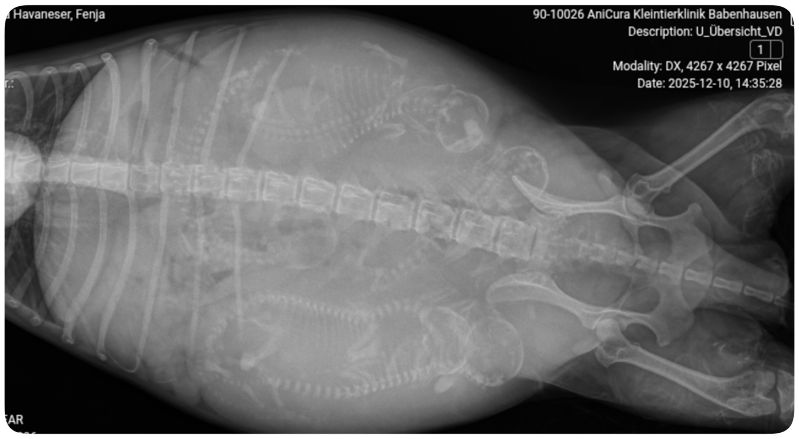

![]()

Fenja wird jetzt geröngt um zu sehen ob was im Geburtskanal liegt.

15h, 5 Welpen sind noch drin, herzschläge sind gut von den Welpen, Fenja bekommt jetzt Oxytozin und Stärkung gespritzt, 45 min warten wir dann noch ob sie es aus eigener Kraft schafft.